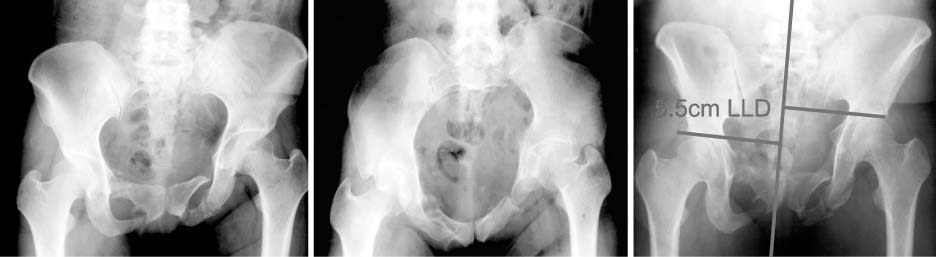

Fig. 3

Two-dimensional computed tomography shows nonunion through the left sacrum and left pubic ramus and 20 degree internal rotation deformity.

Fig. 3 Two-dimensional computed tomography shows nonunion through the left sacrum and left pubic ramus and 20 degree internal rotation deformity.